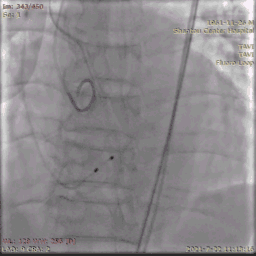

送入输送系统

输送系统定位

输送系统定位,标准位置释放